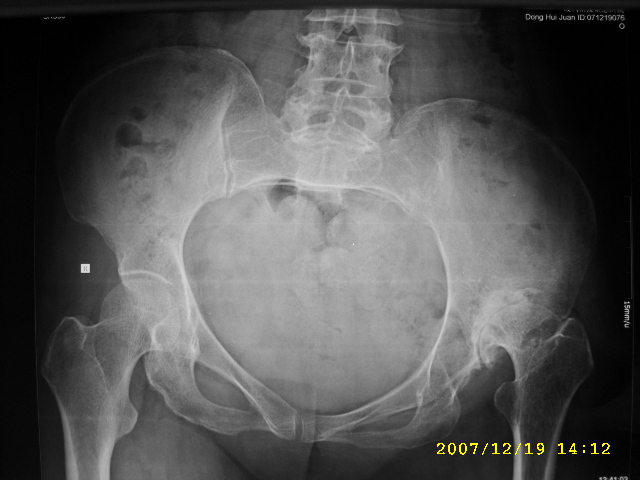

以下是引用逸风在2007-12-19 16:34:00的发言:[br]左侧髋关节间隙变窄,关节面硬化,其下方可见小囊状影,髋臼相对较浅,股骨头未见明显变形,关节面未见塌陷改变;考虑成人髋臼发育不良性骨关节病。